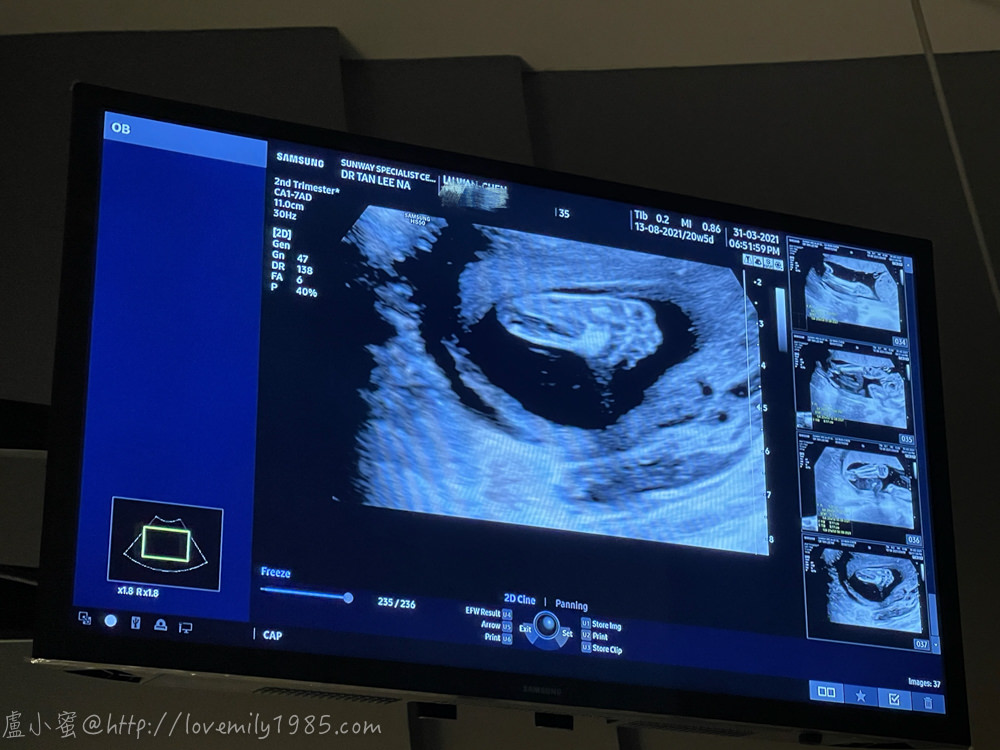

醫生從頭開始照,照到一個如來神腳!!!

高層次超音波

是由專門醫師以高層次超音波檢查胎兒細部構造

用來排除胎兒重大缺陷或畸型

最佳時機在20至24週~因為這時候胎兒大小適中

超音波檢查員易於檢查細心構造

如果超過24週還是可以檢查

但因為胎兒比較大了有些構造因擠壓而不容易觀察清楚

高層次超音波是利用一般的超音波做更仔細的胎兒狀況檢測

除了一般超音波所做的成長測量、胎位、羊水、胎盤位置、重大畸形的檢測外

還加做脊柱、頭、顏面結構、胸腔組織、胃腸、膀胱、腎的大小結構

及四肢等特定的仔細檢查與測量

超清楚的手跟腿!除了檢查身體結構,醫生照了胎盤,說位置很好,可以自然生

也照了子宮頸長度,說夠長不用擔心,羊水量也OK

目前三寶體重約375g,是正常的進展!測量週數也跟實際週數差一兩天而已